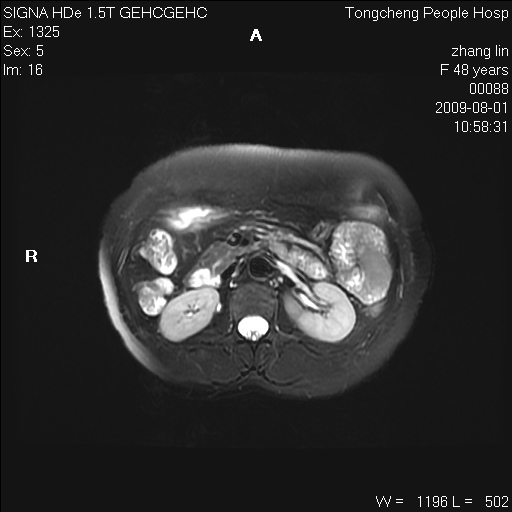

女,48岁。健康体检,彩超发现右肾占位性病变。平素健康。

临床诊断:右肾占位性病变,性质待定(囊肿?肿瘤?)。

上中腹部mr平扫+增强扫描,图像如下:

右肾上极见一类圆形病灶,t1wi呈等信号t2wi呈等高混杂信号,三期增强无强化,边界清---考虑囊肿出血。

同反相位均表现为等信号,病变无强化,考虑含蛋白的囊肿可能,弥散加权相或许有些帮助,